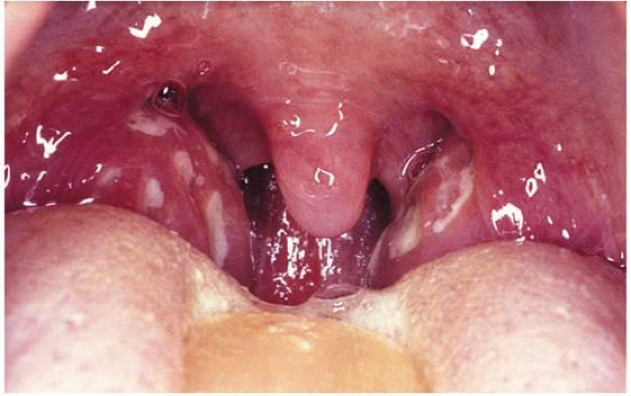

How does this disease present?

Pharyngitis presents as inflamed tonsils with pharygneal exudate with systemic symptoms of sore throat, fever, N/V, and enlarged cervical lymph nodes

symptoms of URI absent